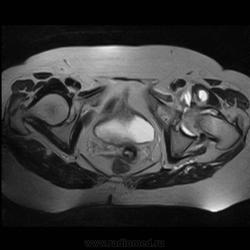

Пациентка 1944г. р. Жалобы на боль области сустава в течении месяца. Температуры не отмечала. Серьезных травм со слов не было. Внешний осмотр новых данных не дал.

Да, аппарат 0,7 только..вы еще брюшную полость не видели).

Да, вряд ли бы пережила.После нашего.Суставы, в принципе, даже ничего получились-не расстраивайтесь.Как с животами обходитесь? У меня в начале пути ( да и сейчас, чего скрывать!) с поджелудочной часто проблемы были....

Настраивайте протоколы и будет супер, аппарат 0,7Т может намного больше, чем вижу тут.